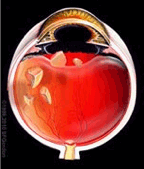

水晶体核落下に対する硝子体手術(左)や眼内レンズ落下に対する硝子体手術(右)や眼内レンズ混濁や度数違いでの眼内レンズ交換術

網膜剥離と白内障同時硝子体手術(左)や白内障のチン氏帯脆弱症例に対する眼内レンズ強膜内固定術(右)

硝子体出血や眼内炎や黄斑前膜など白内障同時硝子体手術(左)や白内障のチン氏帯脆弱症例に対する眼内レンズ縫着術(右)などを行っております。